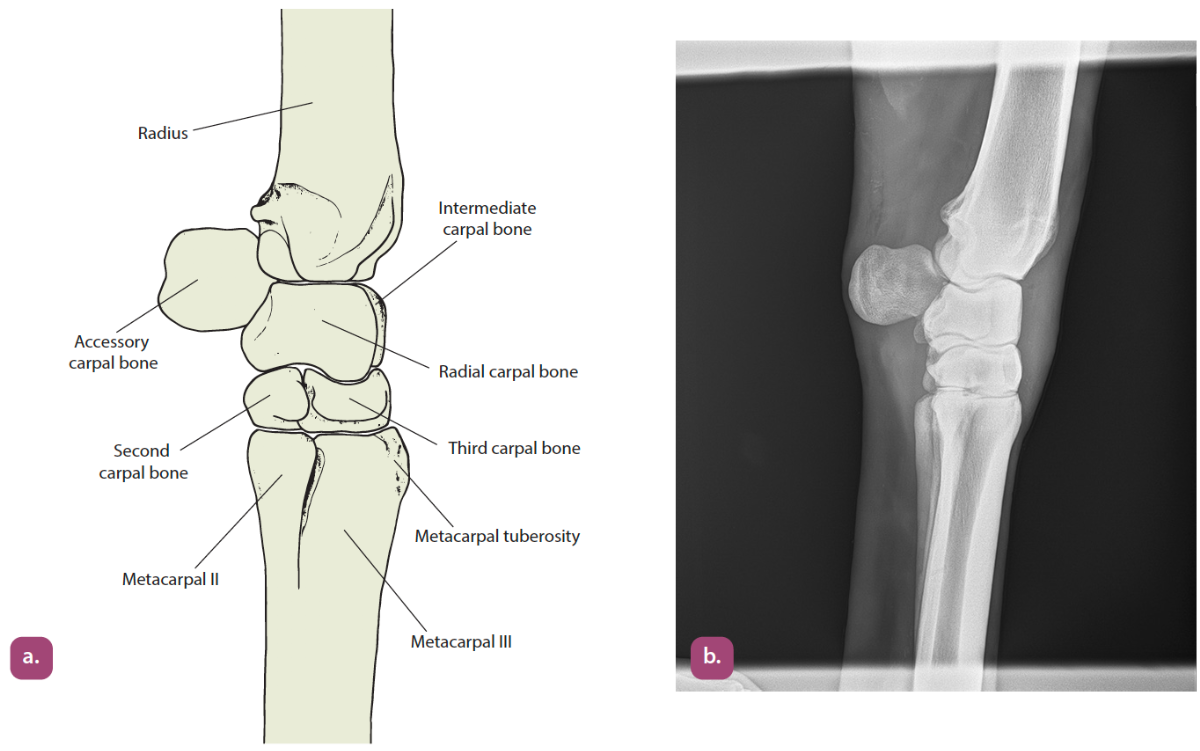

mediolateral projection of the carpus

dorsopalmar projection of the carpus

flexed mediolateral projection of the carpus

oblique projections of the carpus

flexed lateral carpus projection

extended lateral carpus projection

dorsopalmar carpus projection